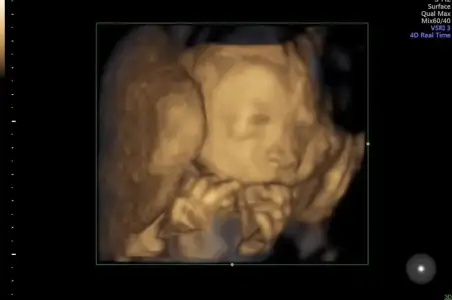

Aç mi gitmiştin ben hep biseyler atistirip gidiyorum her gitmemde yuzu böyle 🙈

Kahvalti ettim bir de üstüne çikolata yedim hadi belki işe yarar diye😂 hastaneye gittiğimizi mi anlıyornmu nedir hep böyle uyuyor😅 eve geldiğimizde tekmelemeye baslıyor dogumda görcez artık yüzünü😂

Detaylı ultrasondan fotoğraflarımız var ama üzerinden 2 ay gecti değişmiştir diye düşünüyorum😌